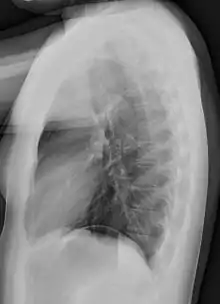

Normal lateral chest radiograph.

Lateral views of the chest are obtained in a similar fashion as the posteroanterior views, except in the lateral view, the patient stands with both arms raised and the left side of the chest pressed against a flat surface.